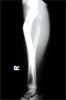

Intra

Op

Ilizarov frame with corticotomy applied